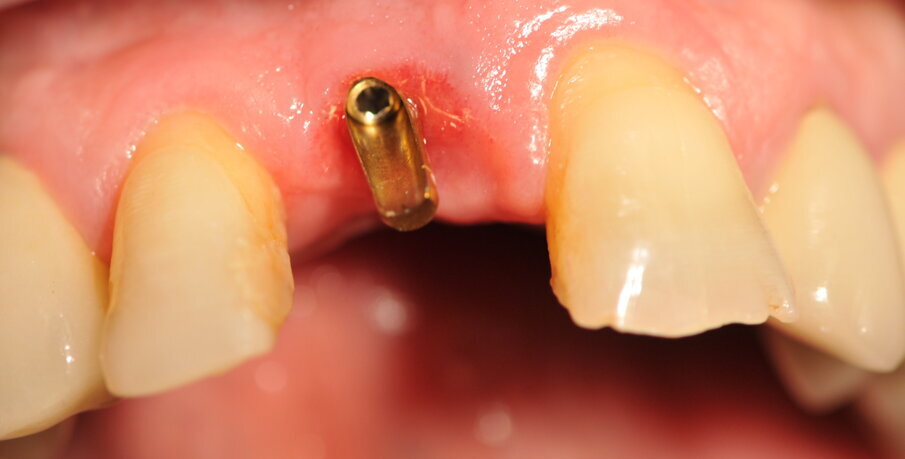

Paziente di sesso maschile di 60 anni di età giunto alla nostra osservazione per una edentulia parziale dovuta all’assenza dell’elemento 1,1. La situazione clinica è resa esteticamente e funzionalmente complicata dalla assenza dell’elemento 2,2 che considerato lo spostamento dei denti contigui comporta un aumentato spazio per la sostituzione protesica dell’elemento 1.1. Si effettua dopo rx di controllo il posizionamento di un impianto osteintegrato GTB diametro 3,6 x 9 mm ,con posizionamento, come da protocollo, 1,5 mm sottocrestale ed inserzione immediata di moncone easy abutment slim 3,4 x 7 mm altezza gengivale 3,5 mm. angolato a 10 gradi (Easy Abutment Slim – GTB Plan1Health Amaro, UD, Italy). Con l’ausilio di una cappetta easy si costruisce e si cementa, con tecnica extraorale, una corona provvisoria in resina acrilica con forma a pontic su elemento 1.1 in modo da eseguire un carico immediato e fornire al paziente una estetica immediata (Figg. 1-3). Dopo 12 settimane ad avvenuta osteointegrazione si provvede all’impronta definitiva eseguita a livello abutment con elastomero di precisione Aquasyl Monophase (Dentsply) e con idonea cappetta easy (GTB Plan1Health Amaro, UD, Italy). La stessa cappetta easy viene utilizzata dal laboratorio odontotecnico come cappetta da sovrafusione garantendo standard di precisione stabiliti industrialmente (Figg. 4-8). La corona costruita in lega preziosa e porcellana viene cementata dopo una settimana, fatte le prove estetiche e occlusali necessarie sul paziente. I controlli a distanza di 4 anni, sia radiografici che clinici, confermano la stabilità dell’osso intorno all’impianto e la mancanza di perdita di tessuto gengivale attorno allo stesso (Figg. 9-11).

Fig. 5_Moncone Easy slim angolato, notare la quantità di tessuto cheratinizzato dopo condizionamento funzionale con corona provvisoria a pontic.